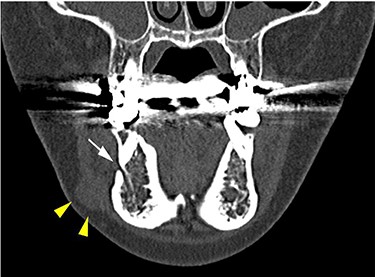

CT findings of a coronal section; yellow arrowheads indicate the schwannoma; the white arrow indicates the mental foramen.

She had a 15-mm, painless, non-pitting and indurated mass at the right mandibular margin (Fig. 1). Oral examination revealed no mucosal abnormalities or swelling. The mass was difficult to palpate from the oral side due to the presence of buccal frenulum on the mucosa over the mass. Magnetic resonance imaging (MRI) revealed a 15-mm nodule with a clear border at the right mandibular margin, with low and high signal intensities on T1- and T2-weighted images, respectively (Fig. 2). Computed tomography (CT) revealed a 15-mm low-density nodule in the right mandibular margin. Calcification, bone invasion or lymph node enlargement were not observed (Fig. 3). The mass was radiologically diagnosed as an epidermoid cyst. The differential diagnoses were schwannoma, neurofibromatosis, pleomorphic adenoma and a powdery mass; however, schwannoma was considered to be most likely.